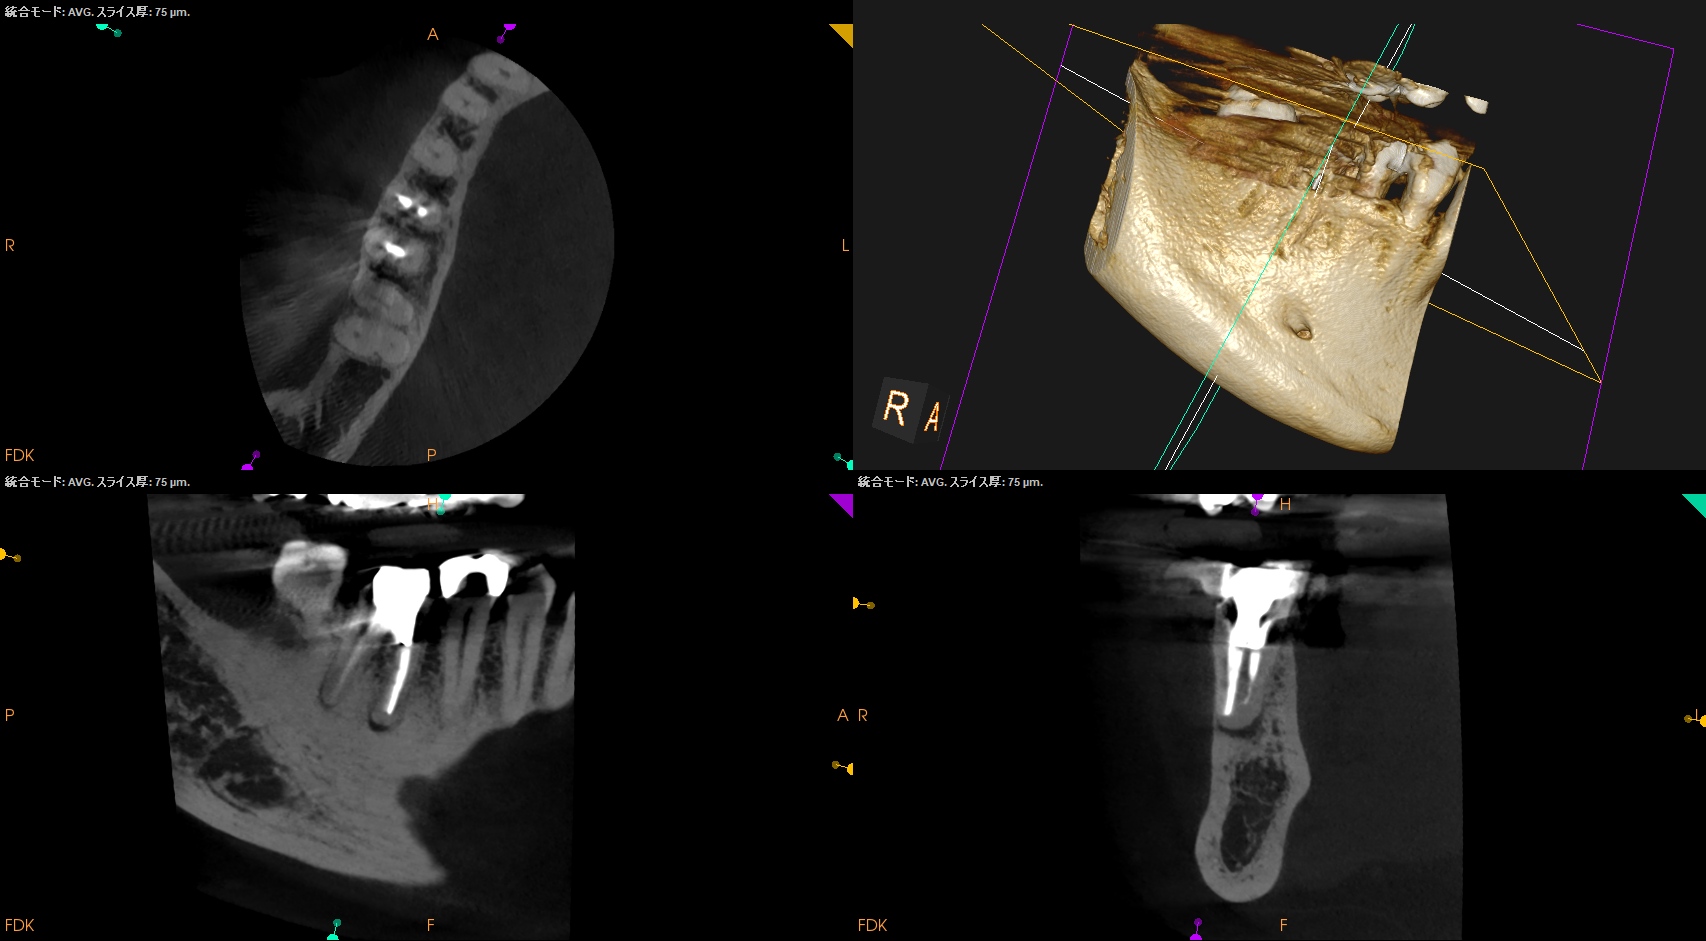

術後にPA, CBCTを撮影した。

MB

ML

D

B

MLは穿通しなかったがこれは細かいGutta Percha Pointが残存したか?破折ファイルの存在か?もしれない。

破折ファイルならば、それは私が折ったのか?前医なのか?はわからないが、

そこにはエンドの予後に与える影響はほぼないことはこのBlogの愛読者?ならご理解いただけるだろう。